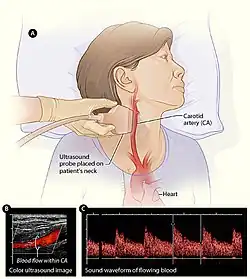

Cerebrovascular disease

Vascular surgeons are responsible for treating extracranial cerebrovascular disease as well as the interpretation of non-invasive vascular imaging relating to extracranial and intracranial circulation such as carotid ultrasonography and transcranial doppler. The most common of cerebrovascular conditions treated by vascular surgeons is carotid artery stenosis which is a narrowing of the carotid arteries and may be either clinically symptomatic or asymptomatic (silent). Carotid artery stenosis is caused by atherosclerosis whereby the buildup of atheromatous plaque inside the artery causes narrowing.

Symptoms of carotid artery stenosis can include transient ischemic attack or stroke. Both symptomatic and asymptomatic carotid stenosis can be diagnosed with the aid of carotid duplex ultrasound which allows for the estimation of severity of narrowing as well as characterize the plaque. Treatment can include medical therapy, carotid endarterectomy or carotid stenting.